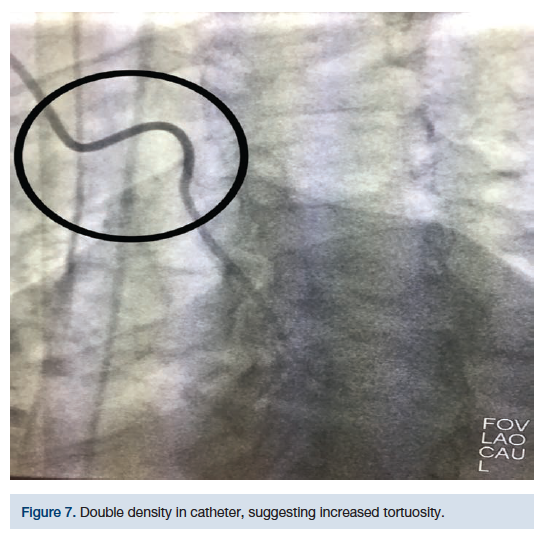

This technique was initially used on a 68-year-old female, diabetic, 5 feet, 4 inches tall, hypertensive, with severe RST (Figures 5-8). Despite several different catheter positions, wires, and extensive deep inspirations, the wire was repeatedly biased towards the descending aorta. Prior to bailing out to an alternative approach, we hypothesized that doing the exact opposite might gain us access to the AA. After several minutes of fluoroscopy and extensive deep inspirations disallowed navigation, a single deep expiration allowed our wire and catheter access into the AA with minimal fluoroscopy.

Upon catheters being placed at the origin of the brachiocephalic trunk or the transverse aorta, the patient is asked to take a deep breath in and “blow” it all out. At that moment, the operator will advance the guidewire in an effort to access the AA. Logic dictates that if a deep inspiration straightens RST for catheter navigation, then a deep expiration would amplify tortuosity, disallowing catheter navigation. While inspiration distends out RST, it also creates a rigid pathway for catheters (Figure 9).

While distended, it is possible this pathway may bias catheters towards the descending aorta. However, a deep expiration “softens” the anatomy, to a small degree, increases the lumen size, and may improve the entry angle into the AA. This may allow a wire to pass into the AA with relative ease. This technique has worked several times on patients that have had severe RST. The “blowout” technique can be attempted when conventional methods of accessing the AA fail and/or when deep inspiration continuously biases catheters towards the descending aorta.